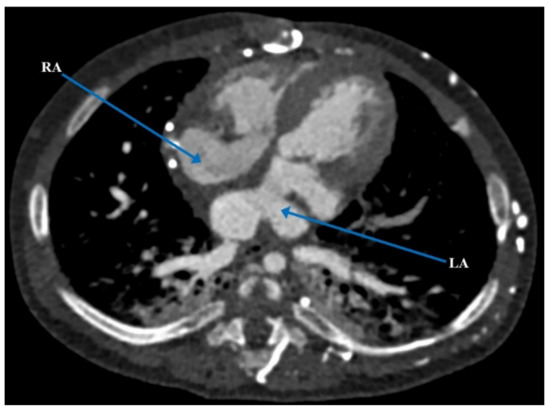

| Present case [6] | Heterotaxy syndrome with partial LPA sling, partial AV canal with a common atrium, atrial situs ambiguous, interrupted IVC, VSD, and PDA | 5 months | PDA occlusion, clipping and division of the anomalous LPA | Defined complex anatomy and surgical plan for biventricular repair | Biventricular repair |